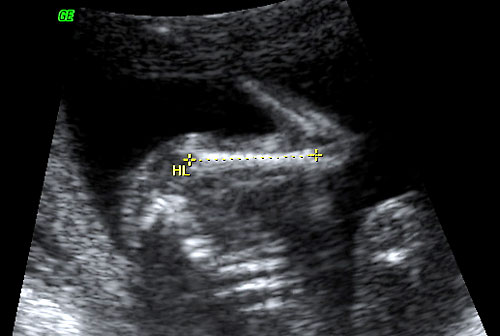

- Nuchal Skin Fold (Benacerraf BR, Frigoletto FD Jr, Laboda LA. Sonographic diagnosis of Down syndrome in the second trimester. Am J Obstet Gynecol. 1985 Sep 1;153(1):49-52)

- Midtrimester (16-22 weeks)

- Edematous integument, with or without fluid collection

- Cut-off value: 6.0 mm